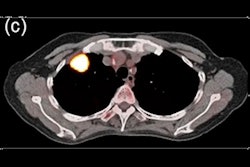

AI can be used in lung cancer imaging applications such as detection of nodules in a screening setting; diagnosis of cancer; classifying cancer subtype; and even predicting treatment response and survival, said Dr. Joon Beom Seo of the University of Ulsan College of Medicine. It can also be utilized to improve radiomics.

Dr. Joon Beom Seo.In the past, computer-aided detection (CAD) and computer-aided diagnosis (CADx) software was developed for detection and diagnosis of cancer, but clinical usage has been limited by a number of shortcomings, including an increased number of false-positive results, Seo said.

However, deep-learning algorithms have been developed that have been shown in testing to perform well in detecting nodules on low-dose CT lung cancer screening exams, according to Seo. In addition, his group has developed an algorithm for detecting subsolid nodules.

As of March 1, 17 commercial software applications have received either the CE Mark or U.S. Food and Drug Administration (FDA) clearance, according to Seo.

"But the real performance of each software in clinical settings is not determined," he said.

As only 3.6% of nodules are actually lung cancer, it's important to determine the risk of malignancy of all nodules detected on CT, Seo noted. A number of researchers have developed AI algorithms to classify nodules by subtype. Another study by Seo's group found that deep-learning software can accurately measure the solid portion of lung cancer.

Furthermore, AI technology can improve inter-reader agreement for LUNG-RADS categorization of nodules, as well as assist in estimating nodule malignancy risk, he said. Other applications include predicting disease-free survival from preoperative CT, assessing prognosis of resectable lung adenocarcinoma, differentiating invasive adenocarcinoma from preliminary invasive lesions, combining a machine-learning algorithm with radiomics to predict immunotherapy response, and detecting important mutations in lung adenocarcinoma. AI can also improve the reproducibility of radiomics, he said.

"AI can be used in almost every step of imaging practice in lung cancer imaging, and although the commercially available software are limited only to the detection and characterization of nodules, I'm quite sure that this [other] research work will be implemented to the clinical practice to be used," Seo said. "So surely AI can enhance our clinical workflow for cancer management in the future."